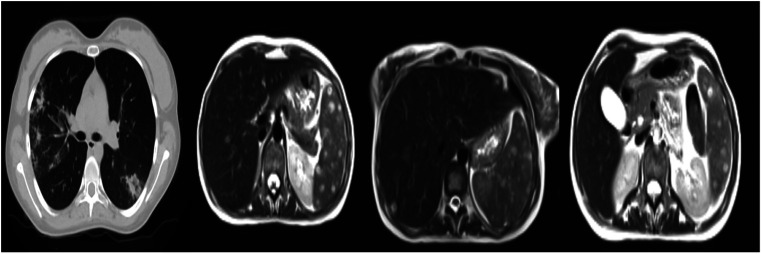

背景:大写Magnusiomyces capitatus (M. capitatus)和棒状Magnusiomyces clavatus (M. clavatus)是引起真菌血症的罕见原因,导致高死亡率,特别是在中性粒细胞减少的血液系统恶性肿瘤患者中。本研究旨在探讨血液学恶性肿瘤合并头状分枝杆菌和棍状分枝杆菌真菌血症患者的临床特点。方法:从2017年10月至2022年11月在atatatrk大学医院住院的患者中分离出8例Magnusiomyces spp,纳入本回顾性观察研究。对8例患者的医疗资料进行分析。结果:5例出现大写Magnusiomyces capitatus, 3例出现clavatus。患者中位年龄为35.5岁。最常见的潜在血液恶性肿瘤是急性白血病。在Magnusiomyces spp.分离期间,所有患者均检测到中性粒细胞值为500个细胞/mm3,其中5例患者出现严重中性粒细胞减少,低于100个细胞/mm3。Magnusiomyces spp.分离前中性粒细胞减少的平均持续时间为29天。7例患者使用棘白菌素、氟康唑和泊沙康唑后出现突破性真菌血症。初始治疗采用两性霉素B脂质体和伏立康唑。总死亡率为37%。所有分离株均对棘白菌素耐药。伏立康唑对各菌株的最低抑菌浓度值最低。年轻患者的生存率较高。在重症监护病房随访的患者死亡率较高。结论:危及生命的Magnusiomyces可在长期中性粒细胞减少的血液系统恶性肿瘤治疗患者中传播。意识到并及时开始治疗可以降低Magnusiomyces spp引起的侵袭性感染的死亡风险。

Background: Magnusiomyces capitatus (M. capitatus) and Magnusiomyces clavatus (M. clavatus) are rare cause of fungemia leading to high mortality rates, particularly in neutropenic patients with hematological malignancies. This research set out to explore the clinical characteristics of patients with hematological malignancies with M. capitatus and M. clavatus fungemia. Methods: Eight patients from whom Magnusiomyces spp. were isolated, from among patients hospitalized at the Atatürk University Hospital between October 2017 and November 2022, were enrolled in this retrospective observational study. The 8 patients' medical data were subjected to analysis. Results: Magnusiomyces capitatus emerged as the pathogen in 5 cases and M. clavatus in 3. The patients' median age was 35.5 years. The most common underlying hematological malignancy was acute leukemia. Neutrophil values of 500 cells/mm3 were detected in all patients during Magnusiomyces spp. isolation, with severe neutropenia at less than 100 cells/mm3 in 5. The mean duration of neutropenia prior to Magnusiomyces spp. isolation was 29 days. Breakthrough fungemia developed in 7 patients using echinocandins, fluconazole, and posaconazole. Liposomal amphotericin B and voriconazole were used for initial treatment. The general mortality rate was 37%. All isolates were resistant to echinocandins. Voriconazole possessed the lowest minimum inhibitory concentration value against all isolates. The survival rate was higher among young patients. Mortality was higher among patients followed up in the intensive care unit. Conclusion: Life-threatening Magnusiomyces spp. can spread among patients with long-term neutropenia under treatment for hematological malignancies. Awareness and prompt initiation of treatment can reduce the risk of mortality in invasive infections caused by Magnusiomyces spp.